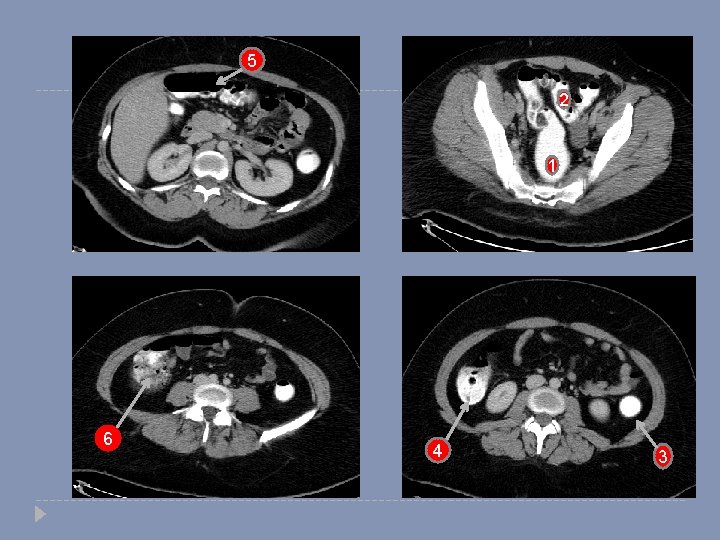

5 2 1 6 4 3

5 2 1 6 1 - Rectum 2 -Sigmoid colon 5 -Transverse colon 4 3 -Descending colon 6 -Cecum 3 4 -Ascending colon